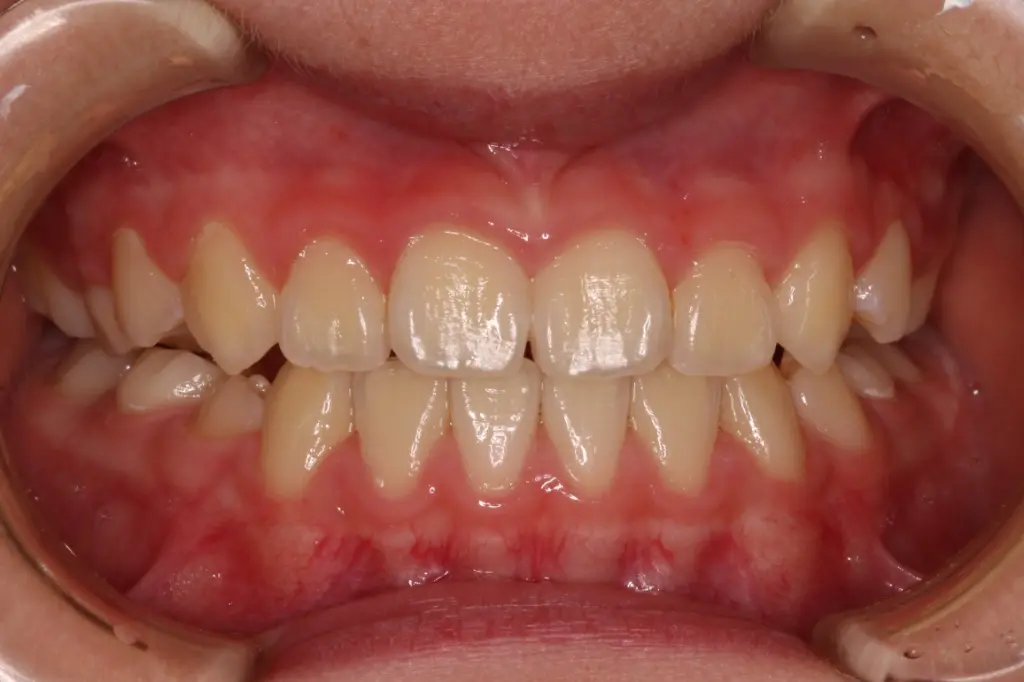

3年経過時

【安定と成長】

反対咬合の後戻りはなく、永久歯への生え変わりも順調です。顎も正しく成長し、安定したかみ合わせが続いています。